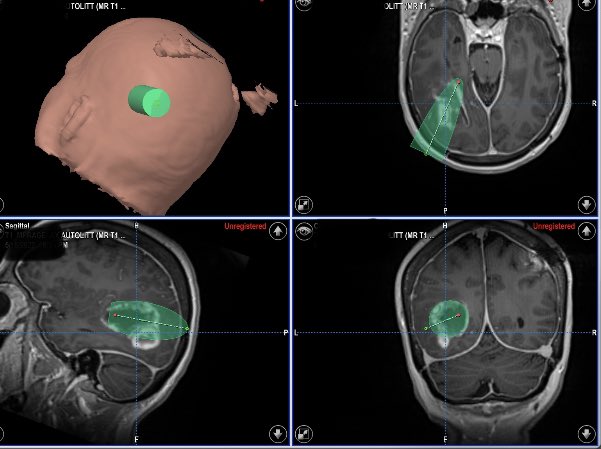

Design a trajectory for LITT (Laser Interstitial Thermal Therapy) for a recurrent GBM @CleveClinicFL @theABTA @BTNcares @BrainTumorAware @dr_mmandel #glioblastoma #braintumorawareness (with patient permission).

English